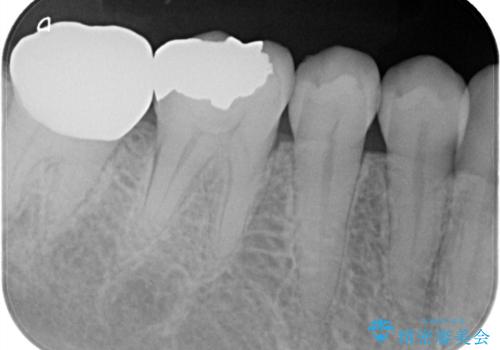

レントゲン写真から古い詰め物が神経と近接している事がわかります。万一に備え、ラバーダムシートを装着しながら治療を行いました。(万が一、虫歯の除去中に神経が露出した場合、神経を唾液から守るため。)

その後、新しい土台を立て、仮歯に置き換えたのち、フルジルコニアクラウンにて治療を行いました。